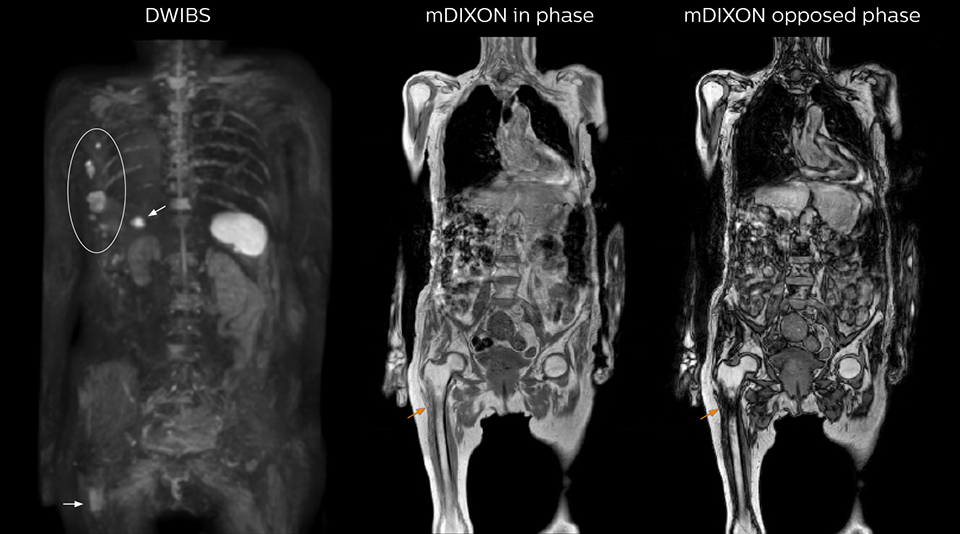

“mDIXON FFE allows us to quickly get information we need to assess the presence of fat. That gives us more information when we need to diagnose bone lesions, and when we are asked to judge fat-containing lesions such as hepatocellular or renal carcinoma,” Dr. Nobusawa says. “The mDIXON fat images can help us to differentiate fatty bone marrow from bone lesions. This is especially useful in elderly people, who tend to have fattier bone marrow. The water images provide a high signal-to-noise ratio in the intestinal canal, which is valuable for visualizing lesions in the colon,” he says.

Kawasaki Sawai Hospital’s whole body protocol also includes an mDIXON FFE sequence. Because mDIXON provides images for four contrast types – water only, fat only, in-phase and out-of-phase – from a single acquisition, it is useful in many ways.

“In-phase and out-phase sagittal T1-weighted FFE images help us to visualize and further characterize bone lesions such as metastasis and bone-marrow hyperplasia that have high signal on DWI. These images are also used throughout radiotherapy, to monitor changes in the fatty bone marrow.”

After implementing the improved whole body protocol, the radiology team initially did not see a large increase in referrals, although Dr. Nobusawa saw clinical cases where the DWIBS images provided him valuable information for diagnosis. This is why Dr. Nobusawa and Mr. Naka started to actively educate referring physicians about the value of whole body DWIBS. They organized several presentations for physicians in the hospital, where they explained how DWIBS can be of value in oncology patients. The information it provides can be useful for physicians when staging cancer, as well as when determining or adjusting treatment strategy. Mr. Naka remembers some cases where DWIBS provided remarkable information. “In one example, DWIBS visualized bone lesions that could not be seen on PET or SPECT. In another case we had found a bone lesion when a normal L-spine scan for narrowing of the disk space was done. One extra DWIBS scan (2 stations, 8 minutes) demonstrated a lesion that later was confirmed to be the primary region of cancer.”